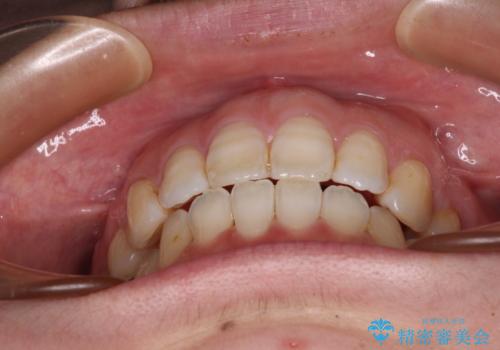

積極的に前歯を牽引したことで、口元の閉じにくさは顕著に改善され、横顔のシルエットが大幅に変化しました。